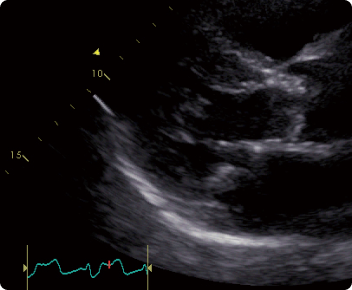

心エコー図検査(超音波検査)

弁膜症診断で最も重要な検査です。弁の狭窄や逆流の有無とその程度、心臓肥大の程度や心機能がわかります。